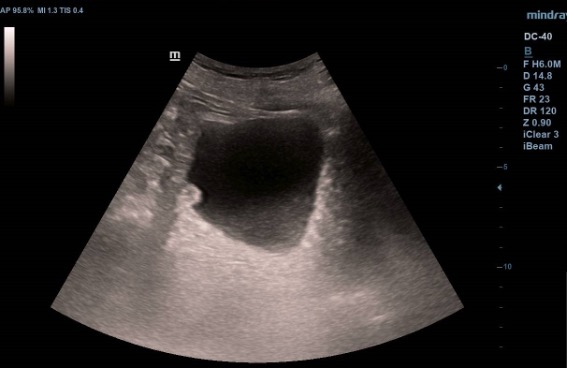

Ecografía vesical: Pared irregular, múltiples lesiones polipoides, la mayor (2.07 cm) en pared posteroinferior. Una lesión polipoiea dependiente de la próstata de 1,6 cm. Otra lesión más craneal en pared posterior de 1.26 cm, y cerca de uréter derecho una de 2 cm.  Además, varias lesiones polipoides más pequeñas en cara anterior y lateral derecha.